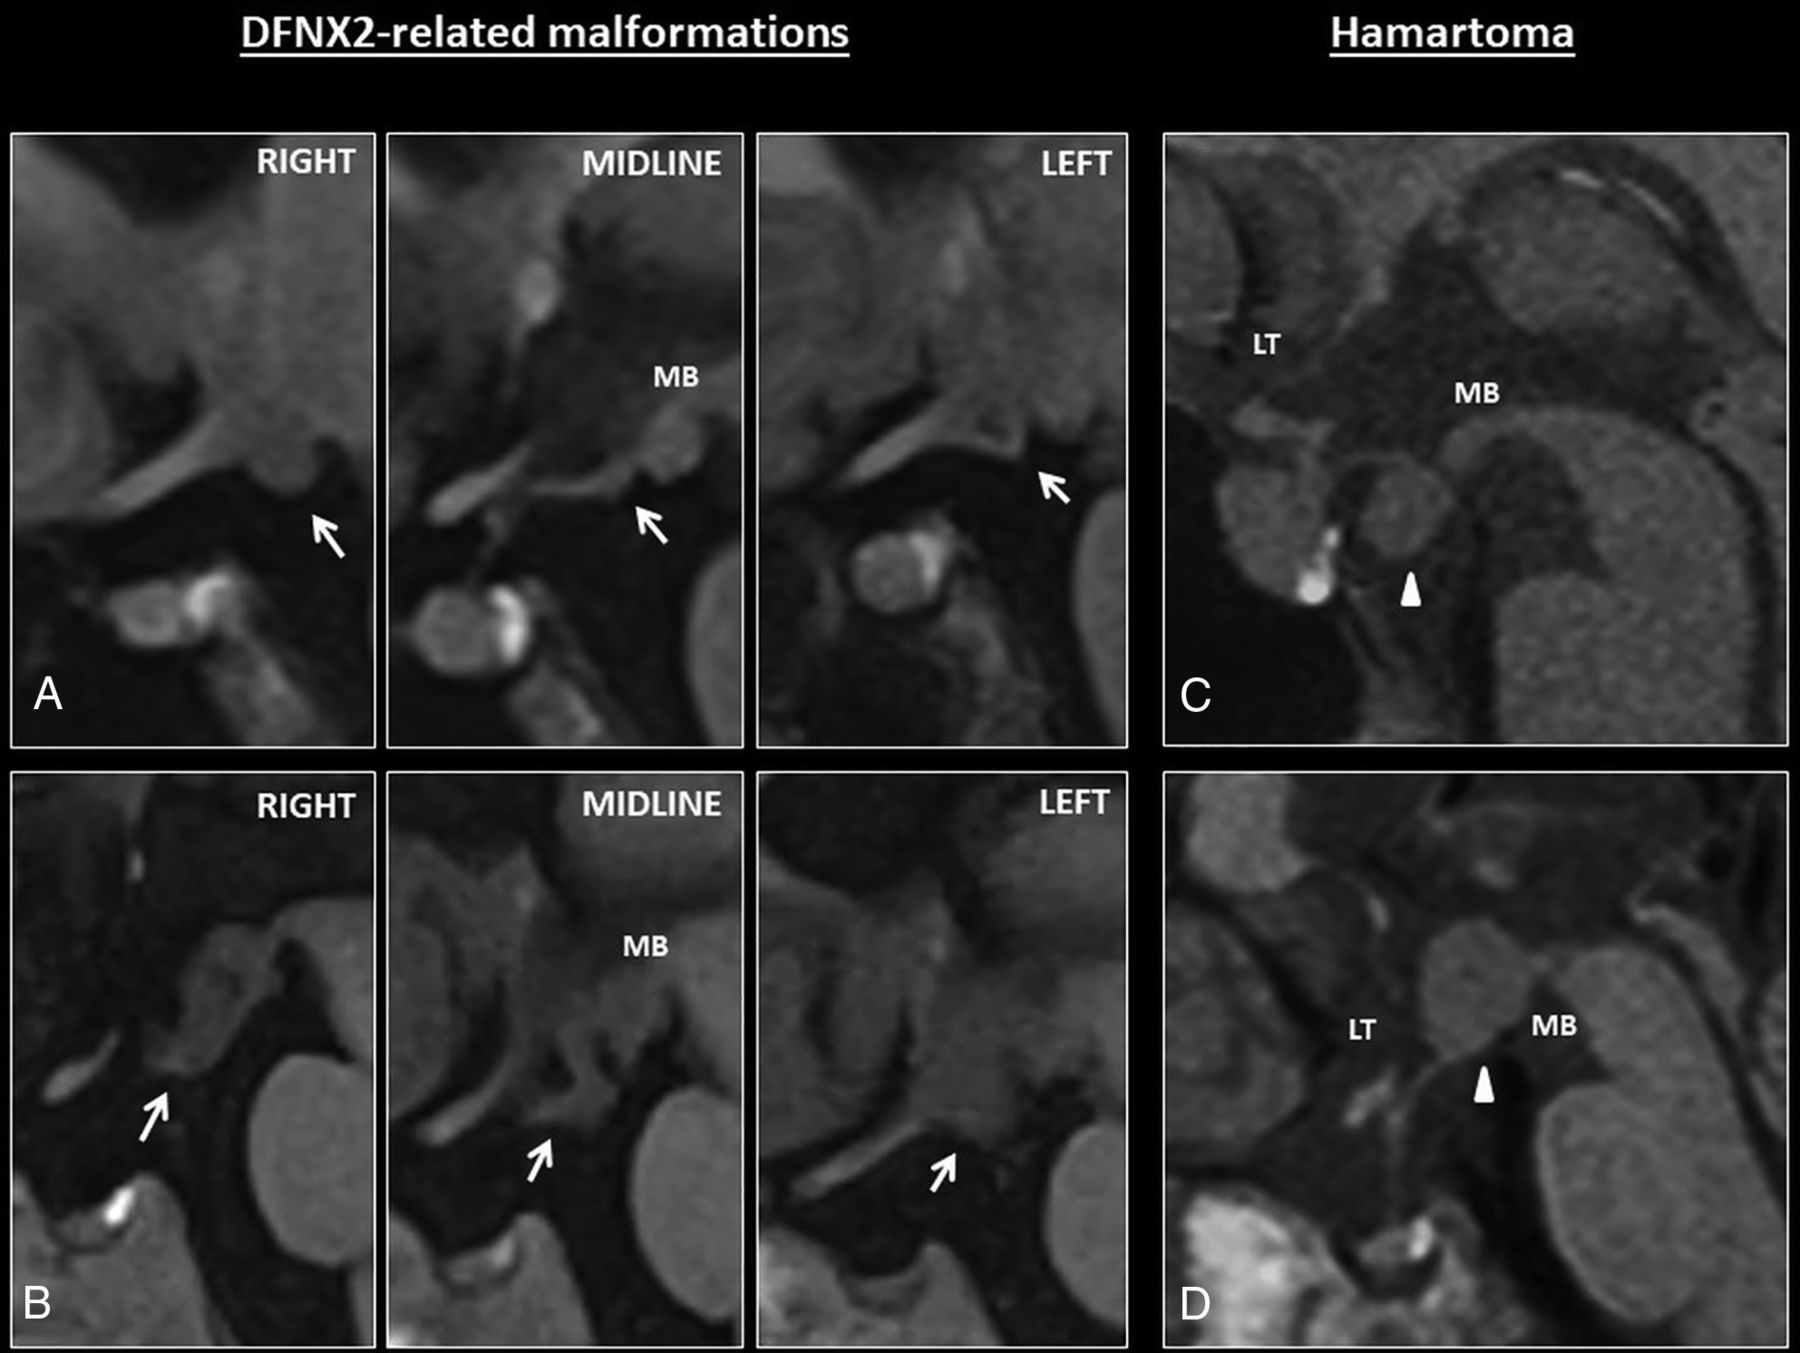

None of DFNX2 hypothalamic malformations showed infundibular, mammillary body, or lamina terminalis involvement (Fig 4A, -B).

A, Sagittal T1 images show mild hypothalamic folding in a patient with DFNX2 (white arrows). This is usually apparent on one of the sagittal slices, such as the left/right one on these series; however, coronal images are better to depict subtle hypothalamic folding. Note the T1-isointense signal of the hypothalamic folding. B, The folding is apparent on all the sagittal images through the hypothalamus. Note again the T1-isointense signal compared with the adjacent brain parenchyma. C–D, Hypothalamic hamartomas tend to be masslike rather than cause hypothalamic folding. They usually arise from the tuber cinereum protruding caudally toward the suprasellar cistern or grow within the third ventricle (white arrowheads) and tend to involve adjacent structures such as the mamillary bodies. MB indicates mamillary bodies; LT, lamina terminalis.